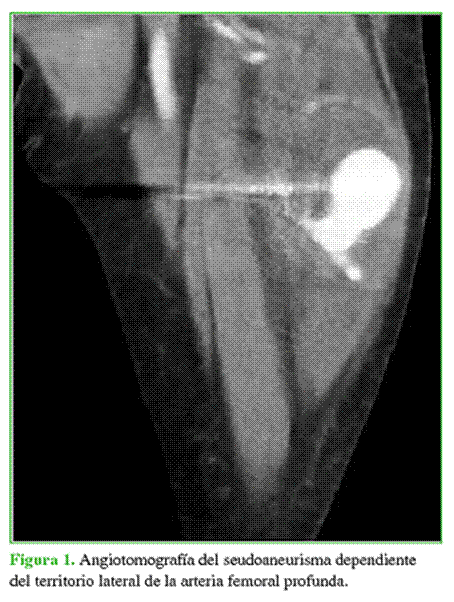

No obstante, a los dos meses de la cirugía, se apreció una disminución del edema de la extremidad y se identificó una masa de aproximadamente 10 cm de diámetro a la palpación, de aspecto fusiforme, elástica y móvil, sin latido ni signos pulsátiles evidentes. Ante estos hallazgos, se decidió completar la evaluación con una tomografía computarizada con contraste (2 de julio de 2018) (Figura 1) en la que se detectó un seudoaneurisma de 4 cm de diámetro parcialmente trombosado en la región anterolateral del muslo izquierdo, a la altura del tornillo de bloqueo distal del clavo endomedular. Este contactaba por debajo con un vaso, probablemente arterial por las características de la lesión, que podía corresponder por su trayecto a una rama descendente de la arteria circunfleja femoral lateral que se origina en la arteria femoral profunda (AFP).